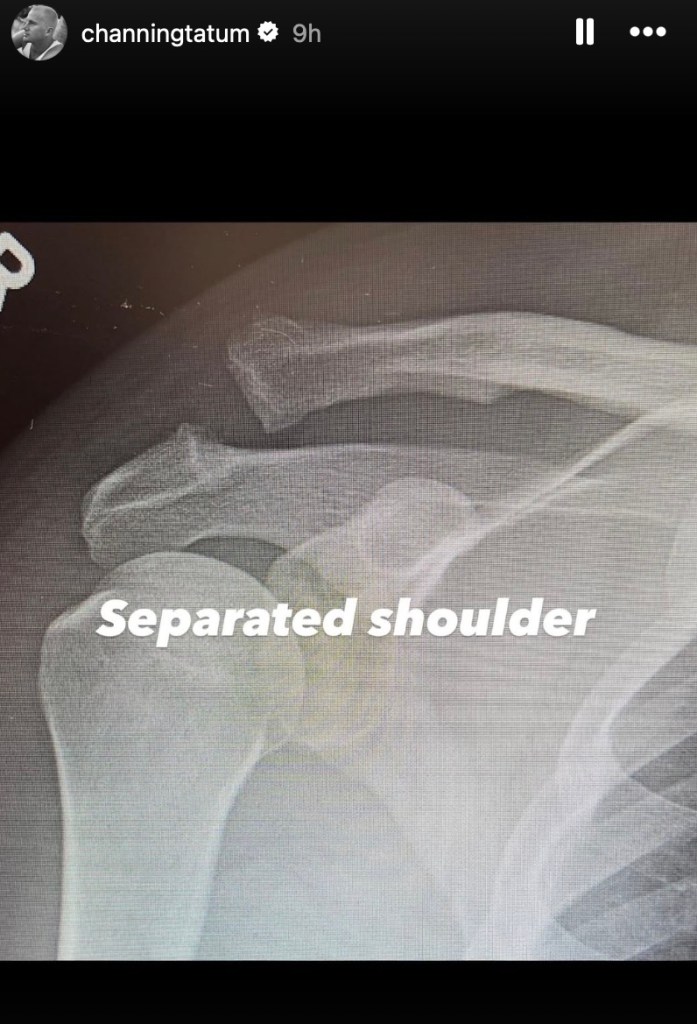

In the first post, Tatum shared an X-ray of his shoulder, clearly showing two broken bones. “Separated shoulder,” he wrote, followed by a second image of the same area after surgery.

“Screwed shoulder. Yay,” he captioned the follow-up X-ray, which showed a large screw holding his bones together.